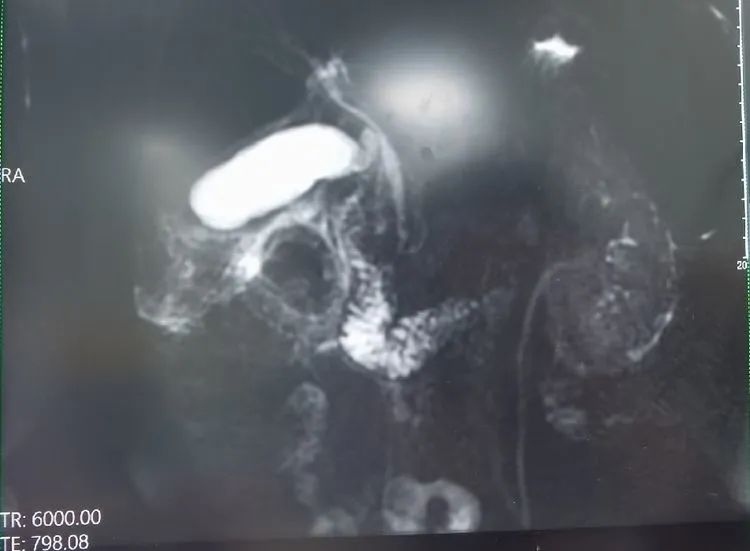

据了解,患者吴先生(化名)因反复上腹部疼痛不适入院,门诊彩超提示:胆囊肿大,胆囊壁毛糙、增厚,胆囊结石,囊内沉积物。入院后进一步完善检查,胸腹部CT示:胆囊多发结石,胆囊炎;胆总管下段小结石,继发胆总管轻度扩张。明确诊断为:胆囊结石伴急性胆囊炎、胆总管结石、急性胆管炎;手术指征明显。广济外科团队凭借丰富的经验,为他制定了先行“ERCP+网篮取石术”再行“腹腔镜下胆囊切除术”的治疗方案。ERCP(内镜下逆行胰胆管造影)后行LC(腹腔镜胆囊切除术),LC术中探查发现:胆囊呈急性坏疽性改变,肿大,积液水肿,与周围网膜,十二指肠等组织致密黏连,解剖界限不清,验证了外科团队对手术方案的制定十分合适,在团队的共同努力下,两次手术均十分顺利。术后第二天,吴先生下床活动平复如故,元气满满。

“我们本次采取的是‘两镜’联合治疗胆囊合并胆总管结石,是我们江永强董事长主持开展《“两镜”及“三镜”联合治疗胆囊合并胆总管结石的临床应用》技术,该技术成功申报我市科技进步二等奖,包括董事长独创开展的三镜联合治疗胆胰疾病更是达到国内先进水平。董事长带领的集团总院外科张军主任和孙敏护士长是我们ERCP团队的精英,东方医院集团普外医疗中心更是凭借该项技术成为我市胆囊疾病治疗领域的佼佼者。”普外科顾冕主任介绍说,“手术方案的选择也是非常重要的,患者手术指征明显,但他本身处于急性期,而且他的胆总管扩张不明显,石头体积虽然不大却正好嵌顿在十二指肠乳头上,导致其胆道梗阻。一旦诱发急性重症胆管炎或者胆源性胰腺炎,就会非常凶险甚至可能会危及患者生命,所以要在最短的时间内解除梗阻恢复胆道通畅。”

如果采取以往常规手术,需要行开腹手术胆总管切口取石及T管引流,不仅创伤大出血多,而且取石成功率低,同时容易引起副损伤。即使手术取石成功,患者仍需T管引流2-3个月以后,才能再次入院行胆道造影,胆道镜拔管。而‘两镜’联合治疗胆囊合并胆总管结石,也就是“逆行胰十二指肠镜ERCP取胆总管结石”与“腹腔镜胆囊切除术LC”联合取石,一个是局麻下从口腔行十二指肠镜,行内镜下网篮取石术,可以最大限度的取净结石;一个是全麻下腹腔镜仅在腹部打小孔进行胆囊切除术。对比之下,“两镜”联合治疗胆囊合并胆总管结石的优势非常明显。不仅明显了缩短患者住院周期,还大大减少了患者的创伤,患者围手术期指标表现更好,术后并发症发生率较低,安全性较高,疗效较好。